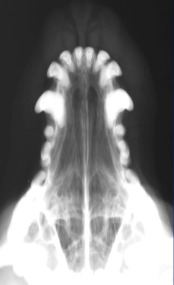

Open Mouth VD view of Nasal Cavity

ID

Ethmoid Turbinates

Maxillary Turbinates

VOmer Bone